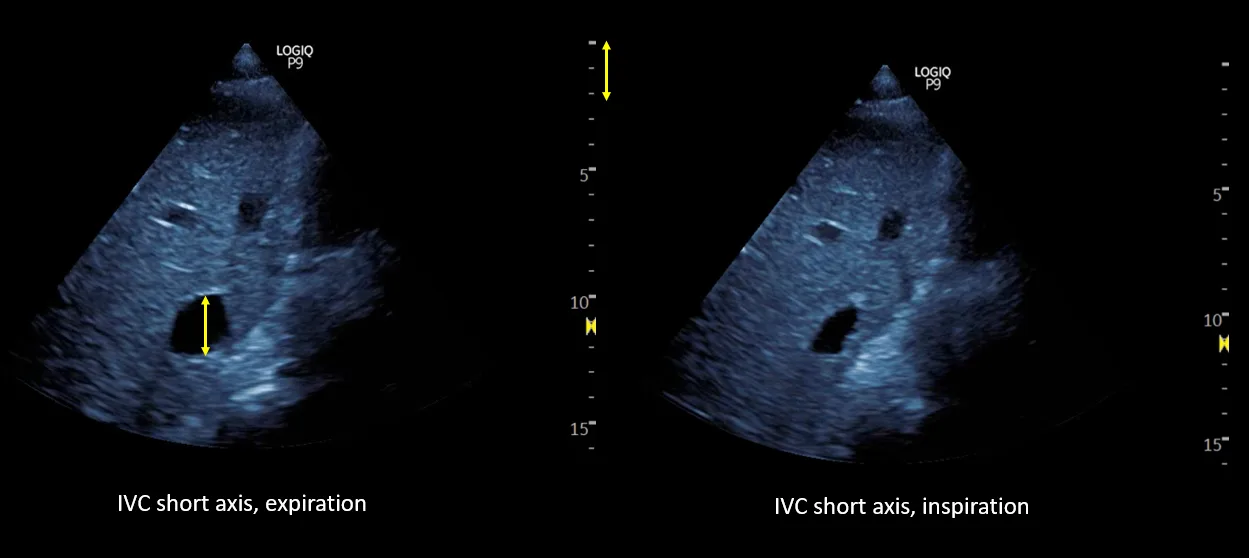

The IVC maximal diameter improved to approximately 2.1 cm, with >50% inspiratory collapse with an estimated right atrial pressure of 8 mmHg (Figure 5). Follow up POCUS after the third session demonstrated further improvement in IVC size (<2 cm), and collapsibility consistent with an estimated right atrial pressure of 3 mmHg (Figure 6). Remarkably, the shape of the IVC shifted from circular to oval during the decongestion of the patient, which is a clinically useful qualitative parameter. Hepatic vein Doppler demonstrated further improvement in S-wave amplitude to near-normal configuration, and the portal vein remained continuous (Figure 7). Intrarenal venous Doppler was not performed, as it is unreliable in ESKD.

Figure 5. Inferior vena cava ultrasound short axis demonstrating the maximal anteroposterior diameter (approximately 2.1 cm) and inspiratory collapse.

Figure 6. Inferior vena cava ultrasound short axis demonstrating the maximal anteroposterior diameter (approximately 1.9 cm) and inspiratory collapse.